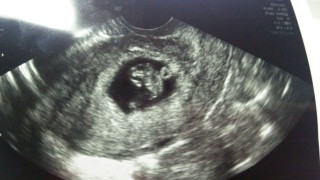

二回目の検診。前回の豆粒みたいな写真から随分人間らしくなりました。卵黄嚢もバッチリ写っていて、栄養をきちんと取れているようでした。丁寧な先生で、様々な角度から撮って下さり、ベストショットを下さいました。

最初の検診から、2週間後に行った時の写真です。ちゃんと育ってるか、すごく不安でした。0.8㎝から1.6㎝に元気に育ってました。 でも、子宮に6㎝の腫瘍が見つかり、ものすごい不安と戦ってます。 無事に子供が生まれてくることを祈るしかないんですけどね。